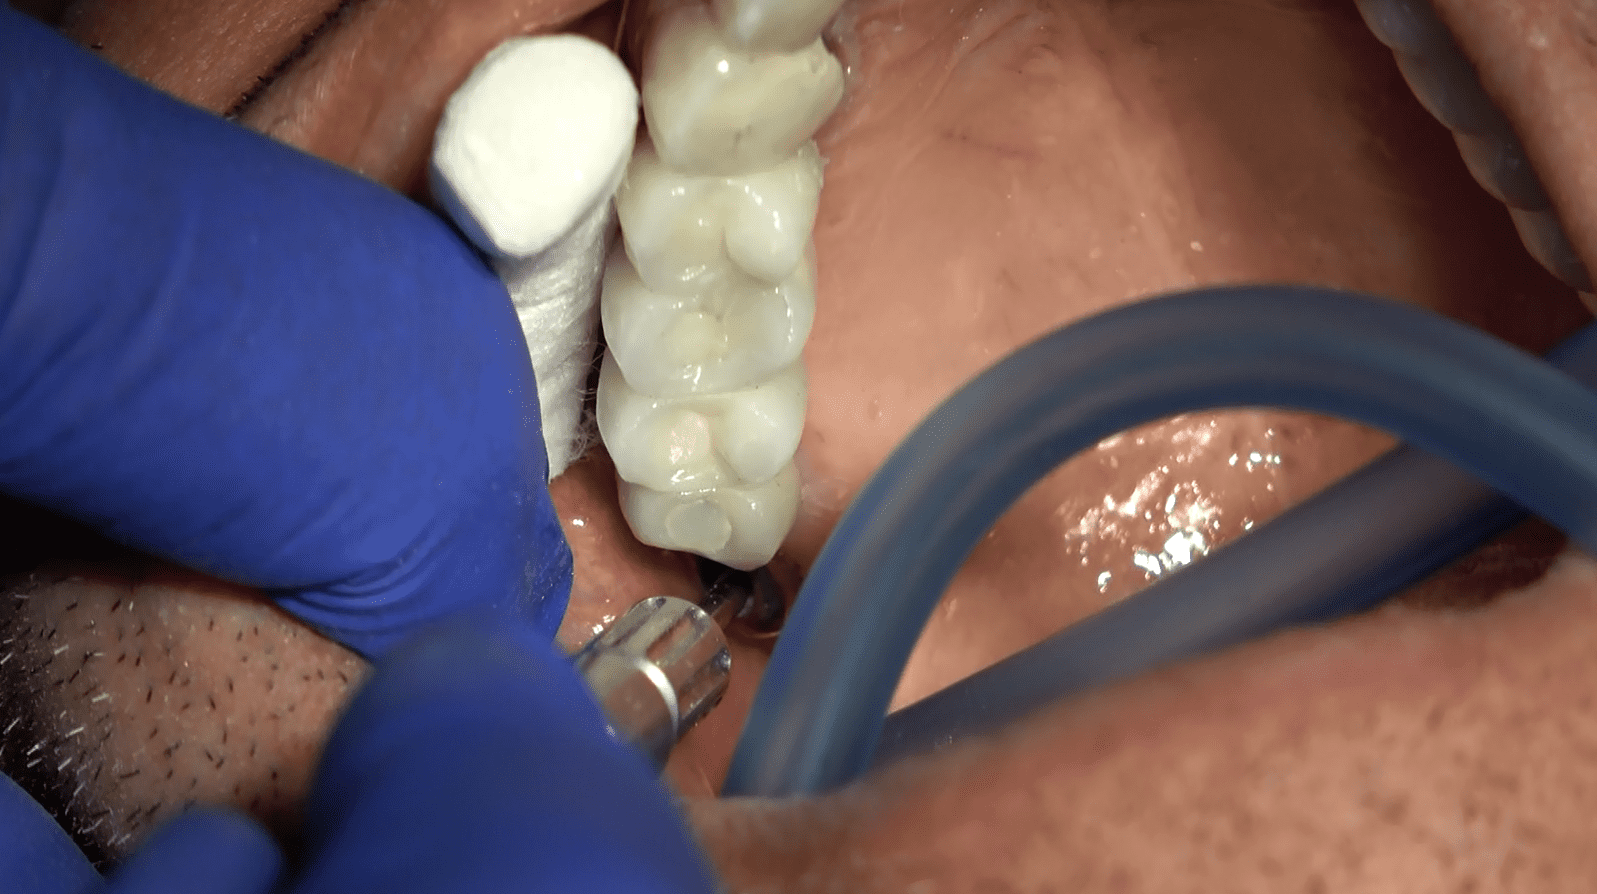

Il nostro team valuta attentamente le condizioni del paziente, registrando le zone con riassorbimenti anomali, atrofie e quelle dell’osso non longilineo. In un’interfaccia diretta tra implantologo e protesista, affrontiamo ogni aspetto negativo, creando un piano personalizzato per il ripristino della masticazione.

Interventi Preventivi per l’Eccellenza Estetica:

Prima dell’intervento implantare, affrontiamo le atrofie e le zone problematiche attraverso interventi preventivi. Il nostro obiettivo è ottenere non solo una funzione masticatoria ottimale ma anche una soluzione estetica preventivata con il paziente. Garantiamo circolari fissi in ceramica senza falsa gengiva, con elementi dentali che emergono naturalmente senza aggiunte antiestetiche.